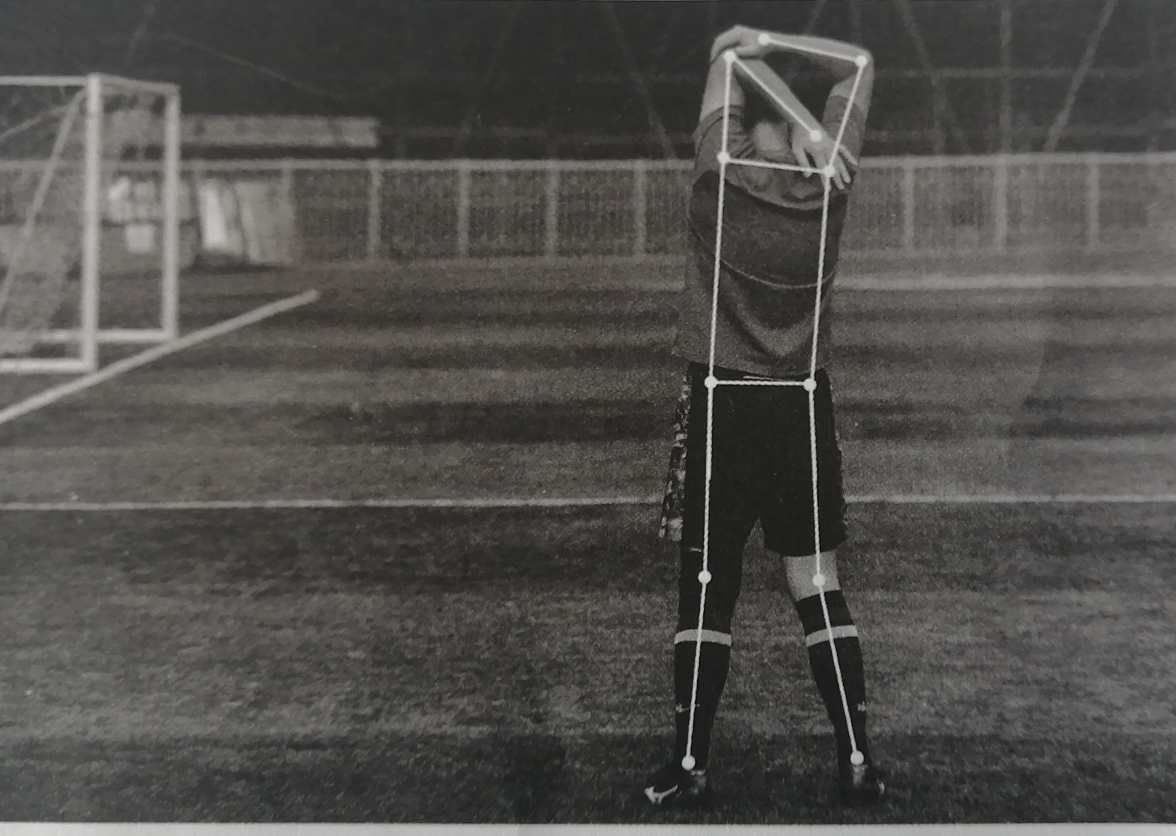

骨骼点标注是将人体运动的关节点进行描点标注,多用于建立健康档案。人工智能通过对骨骼点标注的学习,可以快速锁定病灶关节。如图所示,在一张人体运动图中,对人体关节进行了描点标注。